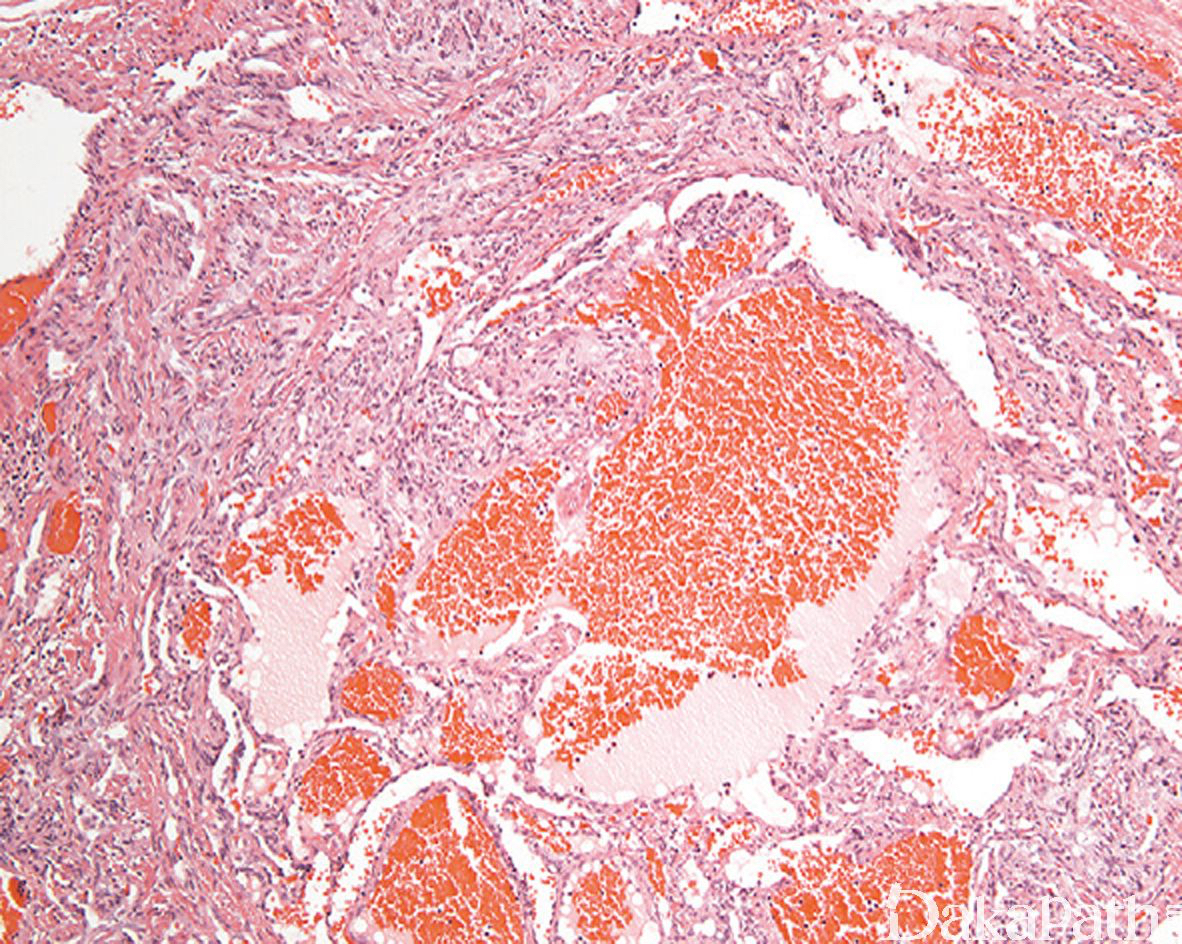

海绵状血管瘤样区域内的血管多为扩张的薄壁血管,大小不一,内衬扁平内皮细胞,常充满血液,可伴血栓形成;

约 50%的梭形细胞血管瘤可见肿瘤于血管内生长,10-20%的梭形细胞血管瘤可完全位于血管内。取决于血管瘤样成分和梭形细胞成分的比例多少,梭形细胞血管瘤在低倍镜下可能类似于海绵状血管瘤或 Kaposi 血管肉瘤;